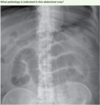

Q

Answer: Haemothorax

Haemothorax literally means blood in the chest, is a term usually used to describe a pleural effusion due to the accumulation of blood. If a haemothorax occurs concurrently with a pneumothorax it is then termed a haemopneumothorax.

It usually occurs from penetrating or blunt trauma to the chest (traumatic haemothorax).